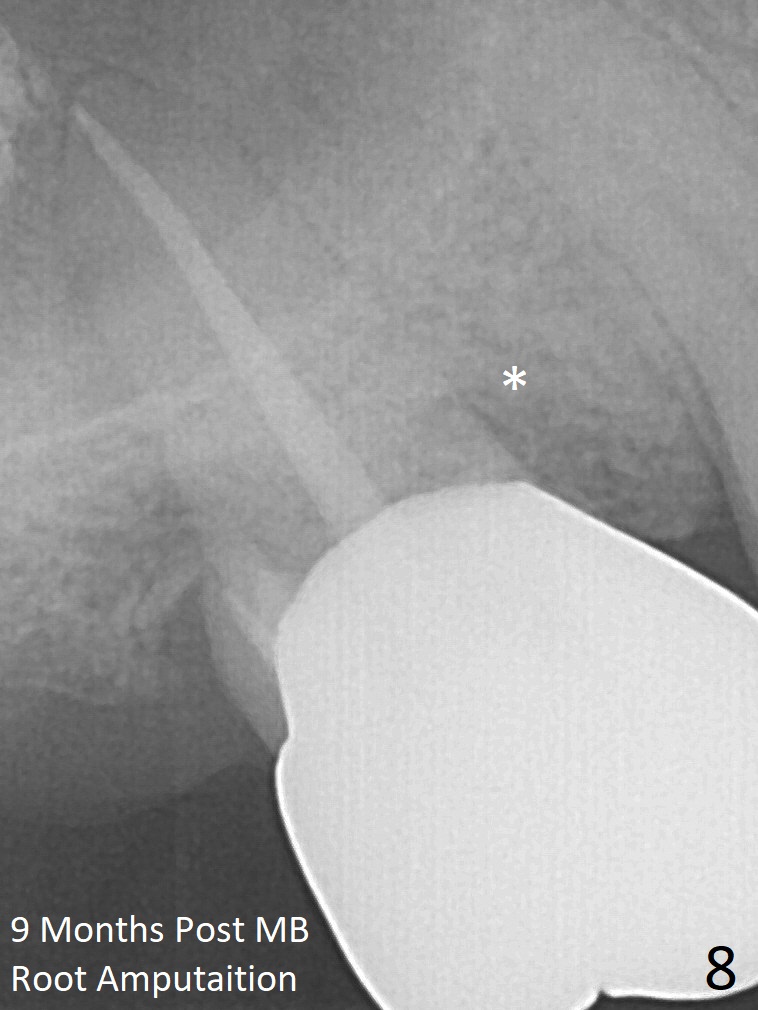

A 56-year-old man has discomfort associated with the tooth #3 one year and a half after root canal therapy (Fig.1: mesiobuccal root vertical fracture). Since an implant is just placed at #19 and another one will be encouraged to be placed at #2 (Fig.2), root amputation may be a valid treatment modality (Fig.3,4). After debridement and Clindamycin topical application, allograft/Osteogen is placed (Fig.5,6 (dashed line)), followed by Osteogen plug (Fig.7 *). Discomfort apparently shifts to the distobuccal root 9 months postop, while the MB defect seems to heal (Fig.8 *). Extraction and implant is expected.